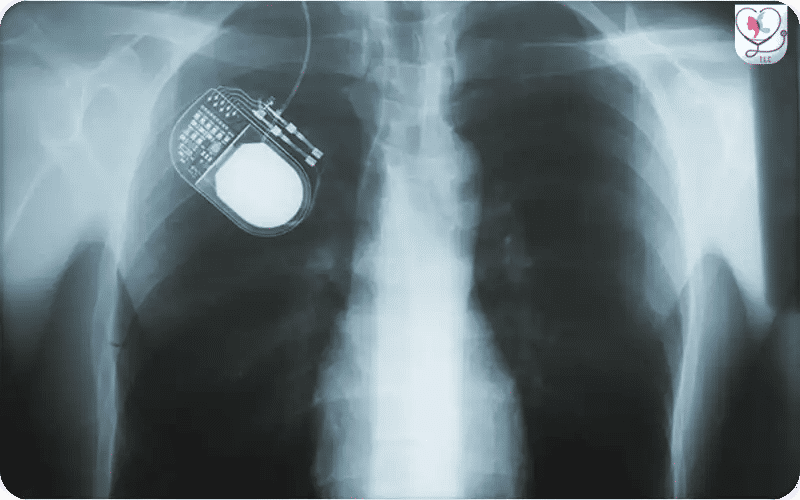

Vista de rayos X de un sistema de Estimulación Cerebral Profunda (ECP) que muestra el generador de pulsos implantado en el pecho. El cable de extensión viaja por el cuello y se conecta a los electrodos intracraneales, proporcionando una perspectiva técnica detallada de la configuración completa del hardware dentro del paciente.

Durante el procedimiento de Estimulación Cerebral Profunda (ECP), el generador de pulsos, un pequeño dispositivo alimentado por batería, se implanta bajo la piel, generalmente en la parte superior del pecho. Este dispositivo se conecta a los electrodos colocados en el cerebro a través de un delgado cable de extensión, permitiendo la estimulación eléctrica controlada para manejar síntomas neurológicos.